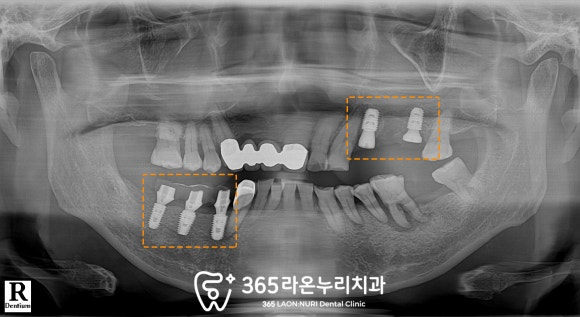

■ 6. 최종 보철

임플란트를 식립했던 부위마다

최종 보철까지 올라가고 난 모습입니다.

왼쪽 위 뼈가 많이 없으셔서

상악동 거상 및 골이식을 진행해 드렸는데

그 부위도 잘 결합되어서

빠른 기간에 잘 마무리가 되었습니다.